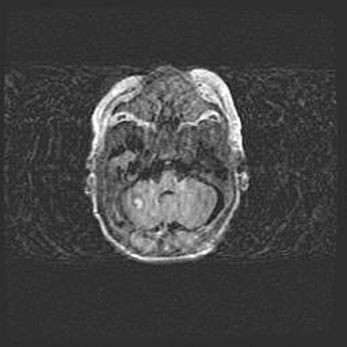

Множественные кисты обоих полушарий головного мозга, наибольшая из них в правой затылочной области. Ассиметричная атрофическая гидроцефалия.

Возраст: 7 месяцев

Вес: 5660 г

Пол: мужской

Окружность головы: 41,5 см

Срок гестации: 28-29 недель

Кисты головного мозга развиваются в результате многоочаговых некрозов вещества мозга и возникают вследствие перенесенной перинатальной инфекции, менингитов, энцефалитов, асфиксии, родовой травмы, расстройств мозгового кровообращения различного генеза. Образованию кист в веществе головного мозга плодов и новорожденных способствуют такие факторы, как высокое содержание в нем воды, недостаточная (или отсутствие) миелинизация и слабая астроглиальная реакция на повреждение.

Кисты могут сочетаться с гидроцефалией и другими поражениями головного мозга.